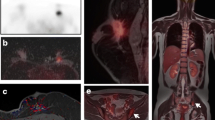

One of the strengths of PET/MRI is that it is highly customizable. The acquired MR sequences can be varied and adapted accordingly to the request of each of the 6–7 bed positions involving the thighs to the vertex that comprise a PET/MR examination. For example, one could run a T2 weighted post-contrast fluid attenuated inversion recovery (FLAIR) sequence during the brain station to look for leptomeningeal disease and diffusion weighted imaging (DWI) during the liver station in the interest of characterizing liver lesions. Research as to which sequences are the most useful overall and at each station is ongoing. Grueneisen et al. found similar sensitivities for PET combined with MR half-fourier acquisition single-shot turbo spin-echo (HASTE) and DWI, PET combined with MR HASTE and T1-post contrast imaging, and PET combined with MR HASTE, DWI, and T1-post contrast imaging (Grueneisen et al. 2017). They noted that reader confidence was significantly higher when a T1-post contrast sequence was included, as would be expected because of the superior anatomic imaging this sequence provides. Melsaether et al. looked at individual organ systems and found that the post-contrast T1-weighted sequence detected more breast, lung, pleural, and brain metastases (Figs. 6.7 and 6.8) than DWI while DWI detected more liver, bone, and nodal lesions than post-contrast T1-weighted imaging (Melsaether et al. 2016) (Figs. 6.9 and 6.10). While the capacity to customize individual stations within a PET/MR examination has not yet been fully explored in the literature, we look forward to what might be on the horizon. Ongoing work will hopefully be able to cut exam time and to improve diagnostic accuracy by finding the most efficient sequences for each station.

48 year-old female with history of metastatic breast cancer. Axial PET (a) , DWI (b), T1 post-contrast (c), and fusion (d) images demonstrate a hypermetabolic 2.5-cm enhancing nodule in the left upper lobe (blue arrow) with restricted diffusion (ADC map not shown), consistent with a lung metastasis. Note the presence of additional lung metastases are best seen on the T1-post-contrast image (c), while a hypermetabolic osseous metastasis in a left rib (green arrow), is most conspicuous on the DWI image (b)

48 year-old female with history of metastatic breast cancer. Axial PET (a) and DWI (b) images demonstrate a hypermetabolic lesion (a) with restricted diffusion (b) (ADC map not pictured) in hepatic segment VI (arrow), consistent with a liver metastasis. The lesion is barely visualized on the T1 post-contrast image (c), but can be seen on fused images due to increased FDG uptake (d)

76 year-old female with history of metastatic breast cancer. Axial PET (a) , DWI (b), Tq post-contrast (c) , and fusion (d) images demonstrate a hypermetabolic lymph node metastasis in the AP window of the mediastinum (arrow), which is more conspicuous on DWI than on post-contrast T1 imaging. Note the presence of a layering small left pleural effusion